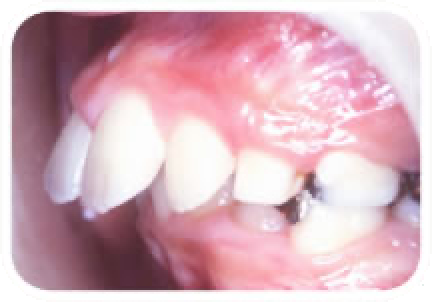

受け口(反対咬合)

上の前歯が下の前歯の後ろで噛んでいる状態です。

遺伝的なものであったり、無意識に下のあごを前に出す癖など原因は様々です。

このまま放置すると下のあごが前にのびやすい状態になります。